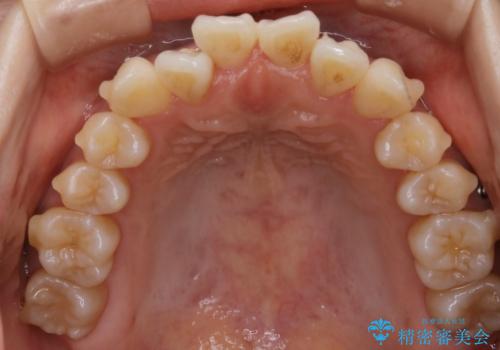

【非抜歯】左右の八重歯・前歯の反対咬合の改善 インビザライン

- 前歯のガタつきを主訴にご来院されました。

診査の結果、骨の厚みに余裕がなく幅の拡大とIPR(歯と歯の間を削り隙間を作る作業)のみでは歯周病に対する不安が残ることが懸念されたため、マイクロインプラントを用いて奥歯から順にすべての歯を後方移動させる方法によってスペースを作ることとなりました。